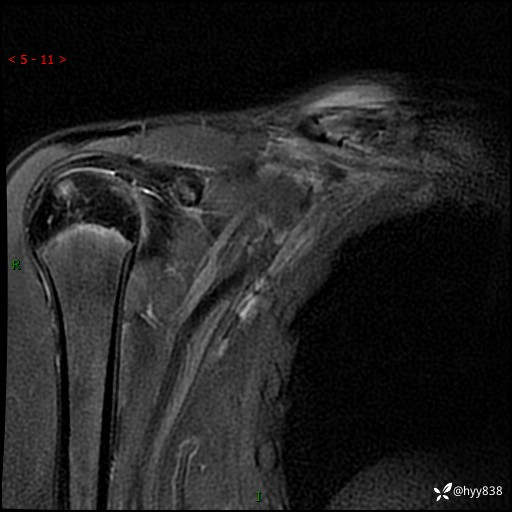

MRI(cor T1WI+T2WIfs+axi T2WIfs)